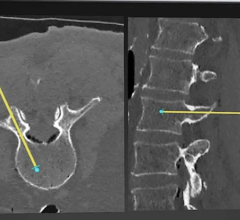

An example of the 3-D vascular roadmapping technology on the Ziehm mobile C-arm systems.

Founded in 2007, Therenva supports physicians in planning and performing minimally invasive endovascular interventions through innovative imaging solutions. The current portfolio includes EndoSize and EndoNaut, a patented solution for intra-operative 3-D navigation and localization of devices providing more confidence, accuracy, and visual comfort during catheterization procedures.

By bundling the leading C-arms of Ziehm Imaging and the EndoNaut solution, physicians already benefit from advanced 3-D intra-operative navigation for optimal guidance in endovascular interventions.